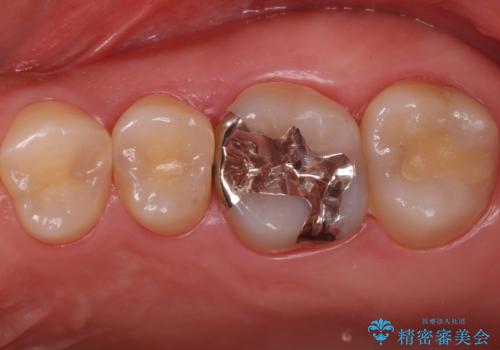

- 症状はないものの、検査の結果右上の奥歯が大きく割れていることが確認されたケースです。

無症状であったため放置していた結果、歯の周囲の骨が溶けてなくなっていました。

今回は抜歯後に骨の補填材を足し、適合の良いブリッジを装着していくこととなりました。